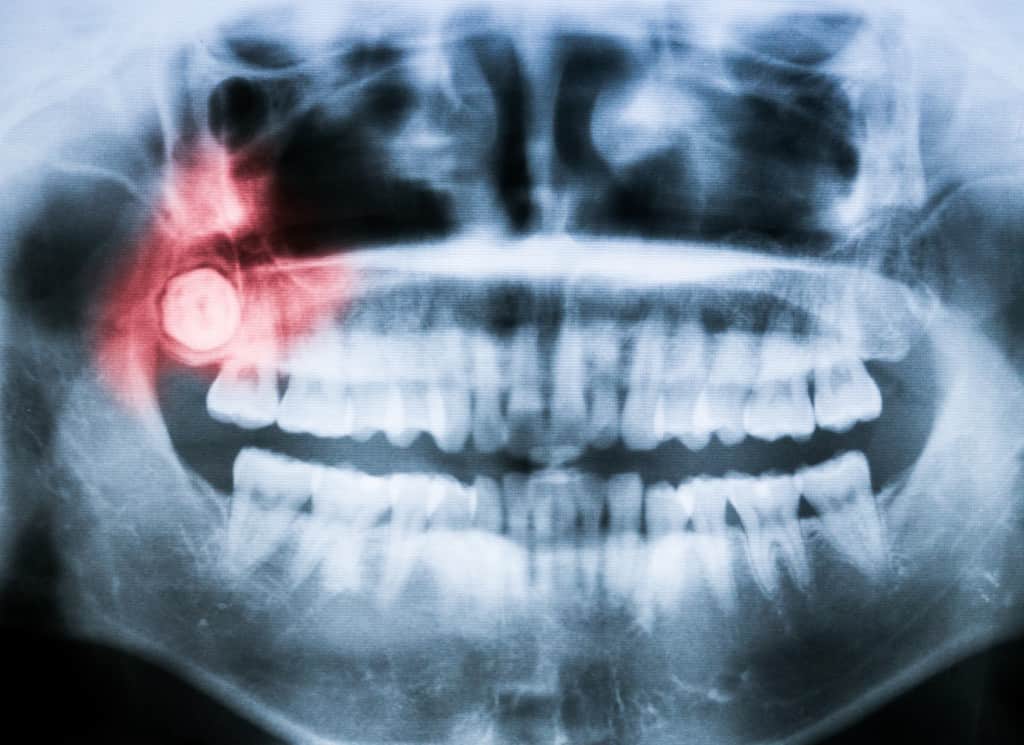

Impacted teeth, particularly wisdom teeth, are a prevalent dental concern that often goes unnoticed until they manifest significant issues. Understanding the symptoms associated with impacted teeth is crucial for early intervention, potentially saving individuals from enduring unnecessary discomfort and complex dental procedures. This article delves into the various indicators that suggest the presence of impacted teeth and underscores the importance of addressing these warning signs promptly.

First and foremost, let’s elucidate what impaction entails. When a tooth is deemed impacted, it fails to emerge fully through the gum line due to physical obstructions or an inadequate amount of space in the jaw. While wisdom teeth are the most commonly impacted, other teeth can experience similar issues. Knowing the potential symptoms can help individuals take proactive steps for their oral health.